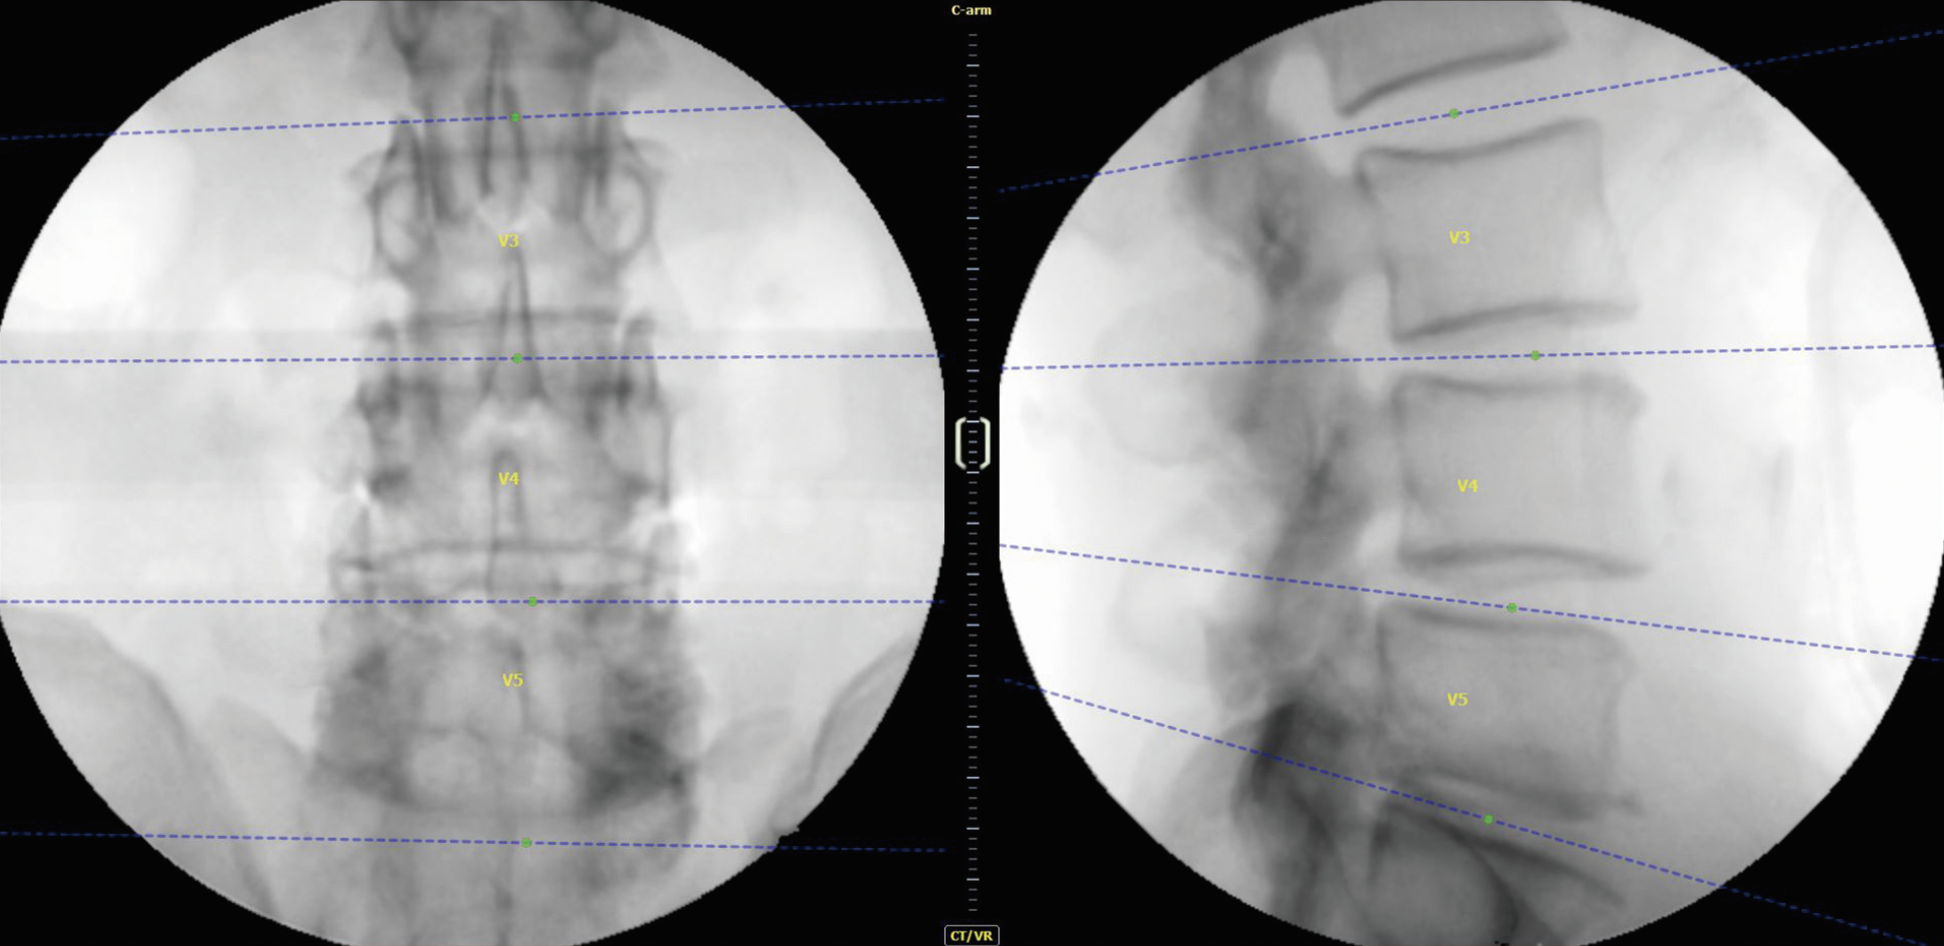

Registro con TC y Arco en C

El registro se realiza mediante una imagen previa de tomografía computarizada (TC) y dos imágenes de rayos X.

Registro 2D y 3D

La tecnología central mejora la precisión y seguridad con un tiempo de configuración rápido. Basado en imágenes de CT preoperatorias y dos imágenes de rayos X intraoperatorias, el algoritmo avanzado de imágenes y el software de reconstrucción completan el registro de manera eficiente.